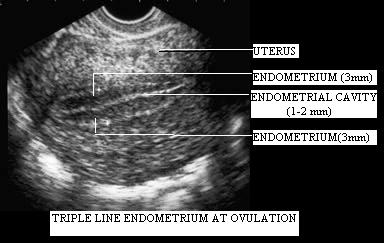

Tu jest ładnie pokazane! Właśnie o tym mówiłam,ze wygląda jak ziarenko kawy - owalne przecięte linią na pół! Czyli to jest to co widać u Ael!

Ja właśnie nie miałam na początku tych białych linii tylko taką plamkę jak u Ael na środku a przy owu widziałam właśnie coś identycznego jak na tym zdjęciu. Mój gin to mierzył i mówił że ma 8mm.